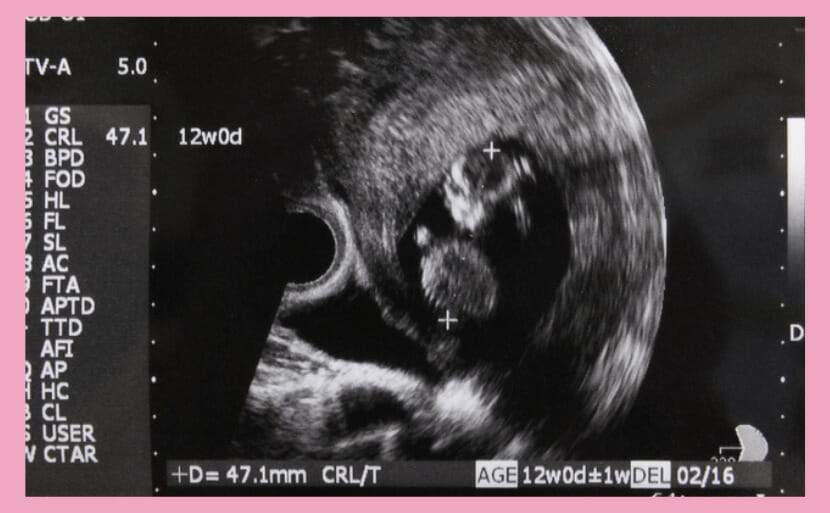

妊娠12周左右的胎儿的平均的大小,衡量胎儿大小的一个标准CRL(Crown-rump length),大约是5〜6cm。

CRL,是对胎儿从头顶到臀部的长度的测量。

超声检查可以让您看到胎儿的发育情况,通过观察胎儿的后颈部、四肢长度和身体其他部位,可以确认是否有21三体综合症(唐氏综合症)这一已知的染色体异常。